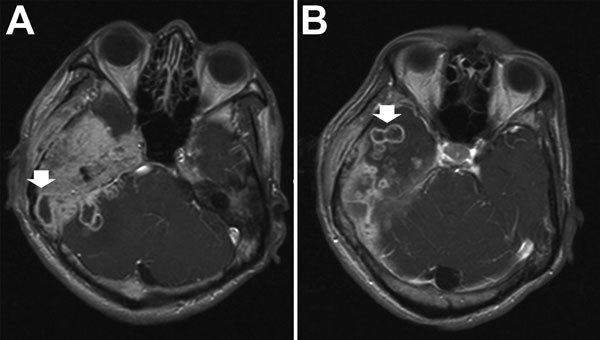

Description:Mycobacterium abscessus complex comprises a group of rapidly growing, multidrug-resistant, nontuberculous mycobacteria that are responsible for a wide spectrum of skin and soft tissue diseases, central nervous system infections, bacteremia, and ocular and other infections. M. abscessus complex is differentiated into 3 subspecies: M. abscessus subsp. abscessus, M. abscessus subsp. massiliense, and M. abscessus subsp. bolletii. The 2 major subspecies, M. abscessus subsp. abscessus and M. abscessus subsp. massiliense, have different erm(41) gene patterns. This gene provides intrinsic resistance to macrolides, so the different patterns lead to different treatment outcomes. M. abscessus complex outbreaks associated with cosmetic procedures and nosocomial transmissions are not uncommon. Clarithromycin, amikacin, and cefoxitin are the current antimicrobial drugs of choice for treatment. However, new treatment regimens are urgently needed, as are rapid and inexpensive identification methods and measures to contain nosocomial transmission and outbreaks.